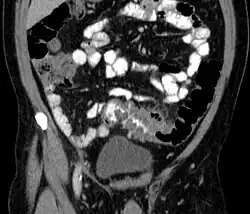

People with the above symptoms are commonly studied with computed tomography, or a CT scan.[38] Ultrasound can provide preliminary investigation for diverticulitis. Amongst the findings that can be seen on ultrasound is a non-compressing outpouching of bowel wall, hypoechoic and thickened wall, or an obstructive fecalith at the bowel wall. Besides, bowel wall oedema with adjacent hyperechoic mesentery can also be seen on ultrasound. However, a CT scan is the mainstay of diagnosing diverticulitis and its complications.[13] The diagnosis of acute diverticulitis is made confidently when the involved segment contains diverticula.[39] CT images reveal localized colon wall thickening, with inflammation extending into the fat surrounding the colon.[40] Amongst the complications that can be seen on CT scan are: abscesses, perforation, pylephlebitis, intestinal obstruction, bleeding, and fistula.[13]